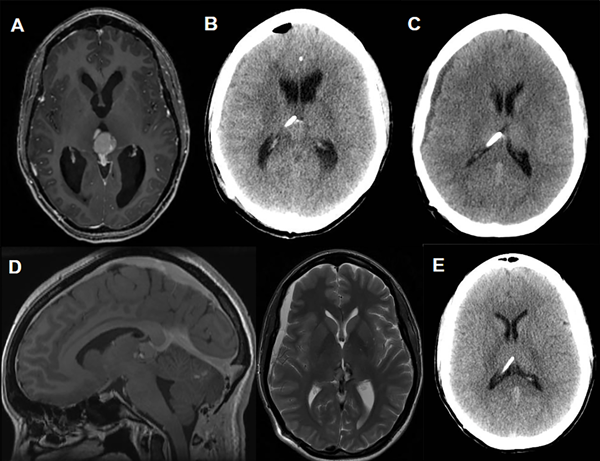

Caso 2 (Fig. 4)

Paciente femenina de 37 años de edad a quien, en contexto de diplopía y cefaleas, se le diagnostica un tumor del III ventrículo con hidrocefalia asociada (Fig. 4A). En este contexto se realizó una tercer ventriculostomía endoscópica con posterior exéresis tumoral. La anatomía patológica informó tumor del parénquima pineal con diferenciación intermedia. A los 15 días postoperatorios, por aumento de la hidrocefalia se decide la colocación de una VDVP Codman Hakim(R) a 140 mmH20 (Fig. 4B). En control por consultorios a los 10 días postoperatorios se evidencia higroma en TC de cerebro por lo que, en subsiguientes controles, se aumenta progresivamente la presión valvular hasta estabilidad imagenológica con reversión del higroma a 200 mmH20 (Fig. 4C - 4D). La paciente se encuentra actualmente estable, sin signos ni síntomas de hidrocefalia ni sobredrenado, con un seguimiento de 75 meses (Fig. 2D).

Figura 4. Caso 2.

Fig A. Resonancia magnética diagnóstica donde se evidencia lesión en región pineal, con intenso realce tras la administración de contraste, que asocia hidrocefalia obstructiva. Fig. B. Tomografía de encéfalo control a las 48 hs postoperatorias de la colocación de la VDVP. Fig. C. TC de cerebro a los 10 días postoperatorios con evidencia de higroma y consecuente aumento de la presión valvular a 170 mmH20. Fig. D. Corte sagital T1 con contraste y axial T2 de RM realizada al mes postoperatorio. Se evidencian signos de hipotensión de LCR (Realce paquimeníngeo, ingurgitación venosa, aplanamiento protuberancial y persistencia de dicha colección subdural). En este contexto se aumenta la presión valvular a 200 mmH20. Fig. E. TC realizada en el último control (follow up 75 meses) sin signos de sobredrenado.